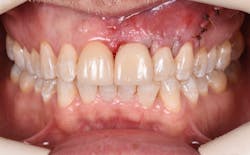

Figure 9: Initial presentation prior to crown lengthening

Figure 10: Immediate post-op hard- and soft-tissue crown lengthening with laser